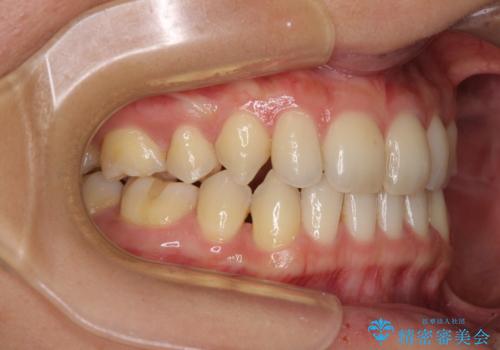

- 以前の矯正治療の後戻りにより、上の前歯にスペースができたことを気にして来院された患者様です。

インビザラインを用いて前歯のスペースを閉じつつ、上下の咬み合わせを構築していくこととしました。

隙間の空いてしまった前歯は、矯正治療で治療を行っても後戻りが起こりやすい傾向にあります。

マウスピースの保定装置をしっかりと装着しても空いてしまうため、細いワイヤーによる保定を併用することで後戻りを防止しています。